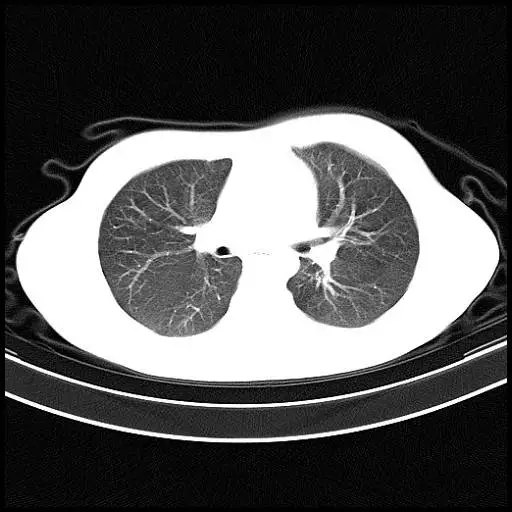

先来看一下正常人的胸部ct:胸廓的横径和前后径的比例是3:2,双肺纹理